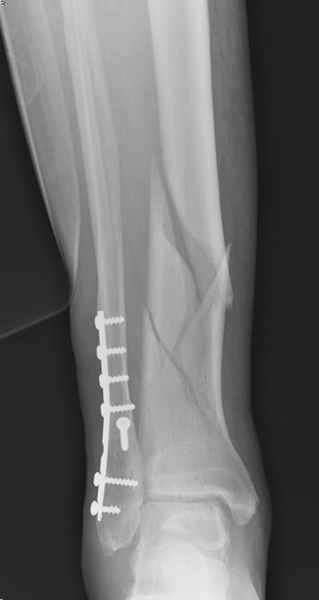

Здесь мы использовали новый Synthes Nail с дополнительными дырками, в проксимальной части 4: по две косых и поперечные (один стандартный а другой динамический), в дистальной части две поперечные, прямая и косая. Вес больного более 120 кг, нагрузку начнем через месяц.

Получилось красиво, поздравляю. Вверху можно было ограничиться одним винтом во фронтальное статическое отверстие, зачем два 45-градусных?

При такий спирали задний край tibia может быть сломан - нет ли этого в данном случае? На всякий случай можно было ввести 1-2 винта 4,5 мм спереди назад мимо гвоздя. Хотя самый дистальный блокирующий винт, возможно, зацепил этот отломок. А какой тут диаметр гвоздя и locking винтов?